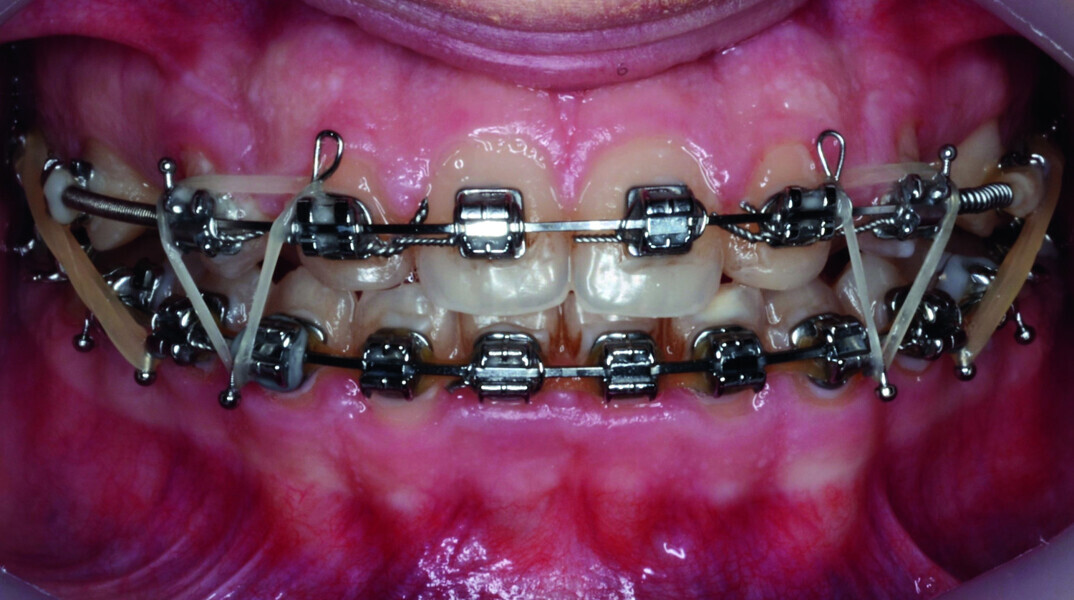

Orthodontic management of maxillary lateral incisors agenesis